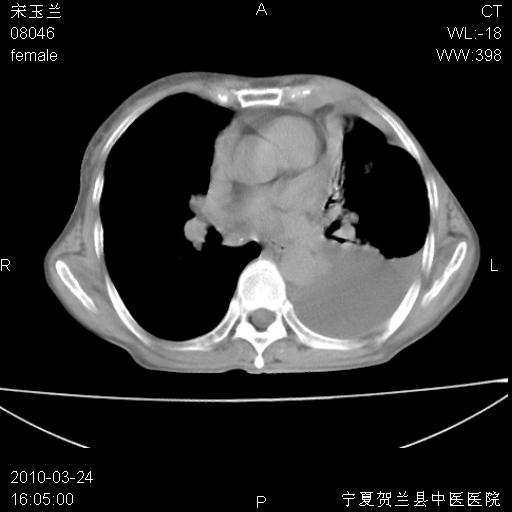

以下是引用zxl51642在2010-3-24 18:49:00的发言:[br]结合乳腺癌术后病史,考虑双肺及纵隔淋巴结多发转移、左侧胸膜转移并左侧大量胸水、左下肺膨胀不全。